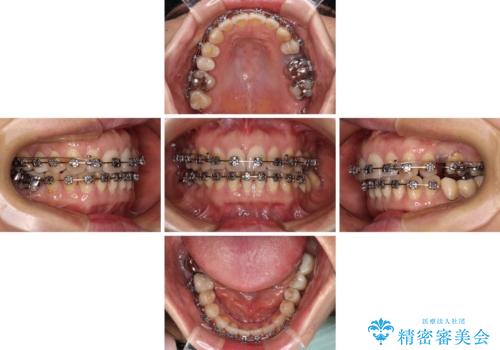

- 飛び出した上顎前歯と正中のズレを気にして来院された患者様です。

上顎正中が右側にずれていたので、むし歯が酷く抜歯が必要な左側臼歯を抜歯して正中を改善することとしました。

左下には新しいセラミックのブリッジが装着されていたため、ブリッジを壊さずに改善できるところまで咬み合わせを改善していくこととしました。

右上小臼歯は銀歯が装着されており、ワイヤー矯正の装置が装着できないため、事前に仮歯に変えてから矯正治療を行い、その後オールセラミッククラウンにて補綴治療を行いました。